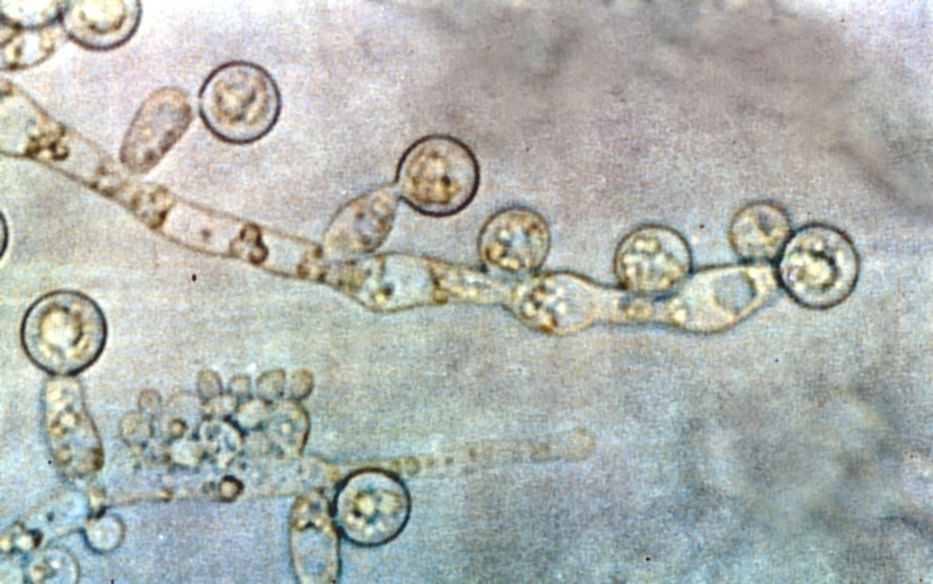

Las infecciones resistentes a los fungicidas incluyen algunas como "Aspergillus", "Candida" o "Trichophyton indotineae", y cualquiera de ellas puede tener impactos muy relevantes en la salud de personas mayores o en pacientes vulnerables.